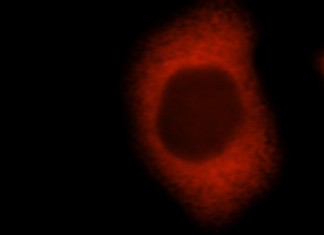

Los científicos descubren los secretos de la resistencia contra el cáncer

Resistencia a los medicamentos es un problema grave para los pacientes con cáncer, con el tiempo, una terapia que una vez fue de algún...